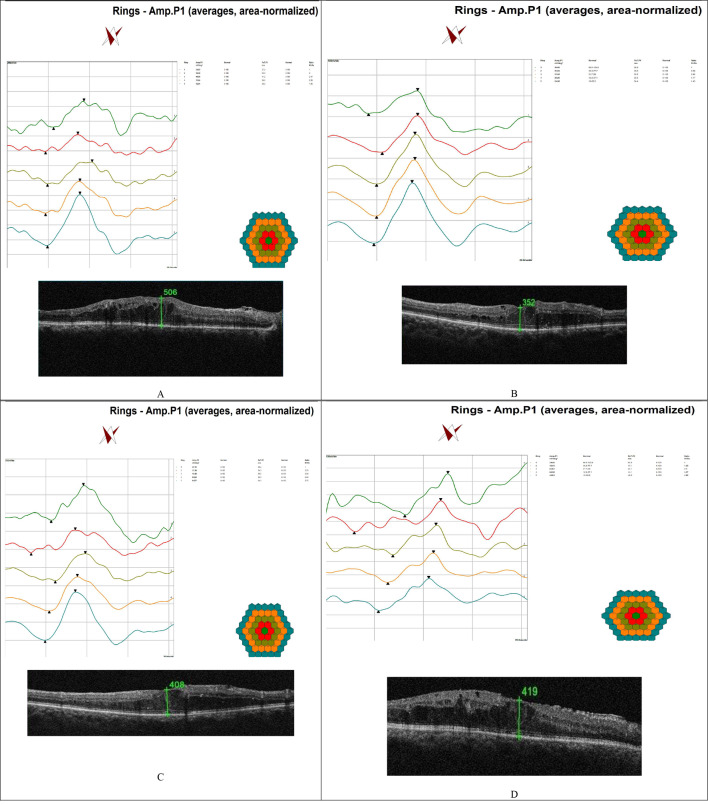

Methods: This prospective interventional study included twenty eyes with refractory DME that were treated using six intravitreal injections of anti-vascular endothelial growth factor (VEGF). The central retinal thickness (CRT) was measured via OCT exceeding 300 μm. The eyes were treated with a single dexamethasone (DEX) implant four weeks after the last injection of anti-VEGF. The outcomes included changes in CRT, BCVA and p1 amplitude of ring 1 on mfERG and intraocular pressure (IOP) recorded before injection and two, four and six months after DEX injection.

Results: The study included fifteen males (75%) and five females (25%). The mean age was 62.83 ± 6.34 years, with the mean duration of diabetes was 16.7 ± 2.21 years. During the two-month follow-up, there were statistically significant reductions in CRT and logMAR BCVA as well as an increase in p1 of ring 1 on mfERG (P = 0.046, P < 0.001 and P < 0.001, respectively). At four months, these changes were not statistically significant (P = 0.99, P < 0.56&P < 0.58), whereas at six months, all the parameters nearly reached pre-DEX injection values (p = 0.93 P = 0.99 P = 0.81). The IOP values were not significantly increased at two, four or six months (p < 0.06, P = 0.35 and P = 1.0, respectively). There were significant negative correlations between the mfERG and OCT parameters before and six months after DEX injection (p = 0.000).

Conclusion: A single intravitreal injection of DEX in refractory DME patients induced significant anatomical and functional improvements, but these improvements only lasted for short periods of up to four months. This treatment exhibited an excellent safety profile. However, at six months, the therapeutic effect was null. The utility of mfERG as a sensitive biomarker of treatment efficacy was highlighted herein.